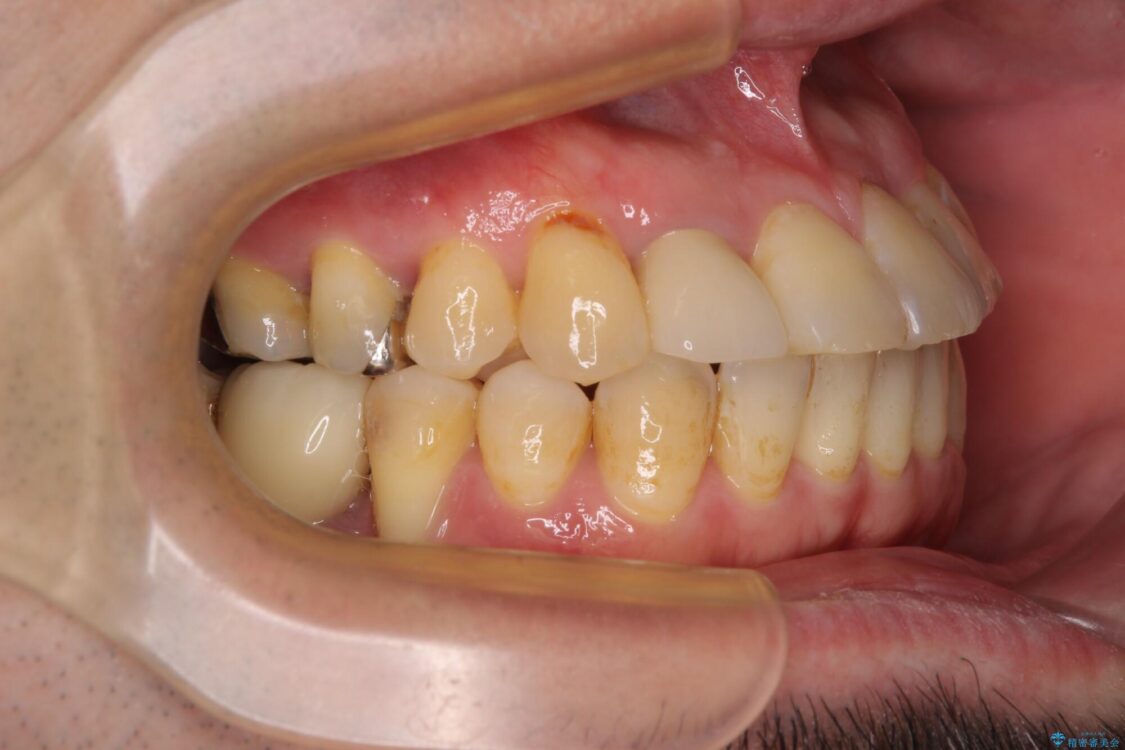

奥歯の痛みと前歯のデコボコを気にして来院された患者様です。

左右下顎の大臼歯は、ともに歯根が破折しており、抜歯が必要な状態でした。

放置したことで炎症による骨吸収が顕著であるため、骨造成を併用してインプラント埋入を行うこととしました。

咬み合わせは受け口傾向であり、上顎前歯の叢生が顕著であったことから、第1小臼歯抜歯による矯正治療も検討しましたが、下顎大臼歯を左右ともに抜歯するため、非抜歯による矯正治療を行うこととしました。

治療前